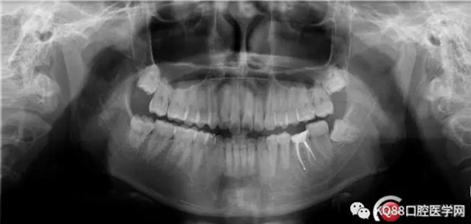

第四步:試尖片。四個(gè)根管,錐度良好,牙膠尖到位。

7.png

8.png